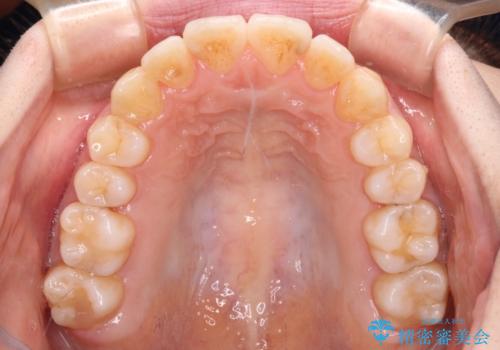

【モニター】前歯の前突感とクロスバイトをインビザラインで改善

- 前歯の突出感とクロスバイトが気になり、インビザラインによる矯正治療を希望して来院された患者様です。

上顎側切歯(上の真ん中から2番目の歯)が舌側転位している場合、インビザラインでは仕上げきれないことが多く、更には無理して動かそうとすると歯髄壊死を起こすリスクが高いと言われています。

インビザラインで歯列を移動する前に、上顎前歯をワイヤー矯正で整え、その後上下歯列をインビザラインにて矯正治療を行うこととしました。

舌側転位している側切歯特有の、切縁の位置が不揃いであったり、根元が内側に引っ込んだ状態であったりという、インビザライン独特の仕上がりになることなく、きれいに整った歯列とすることができました。